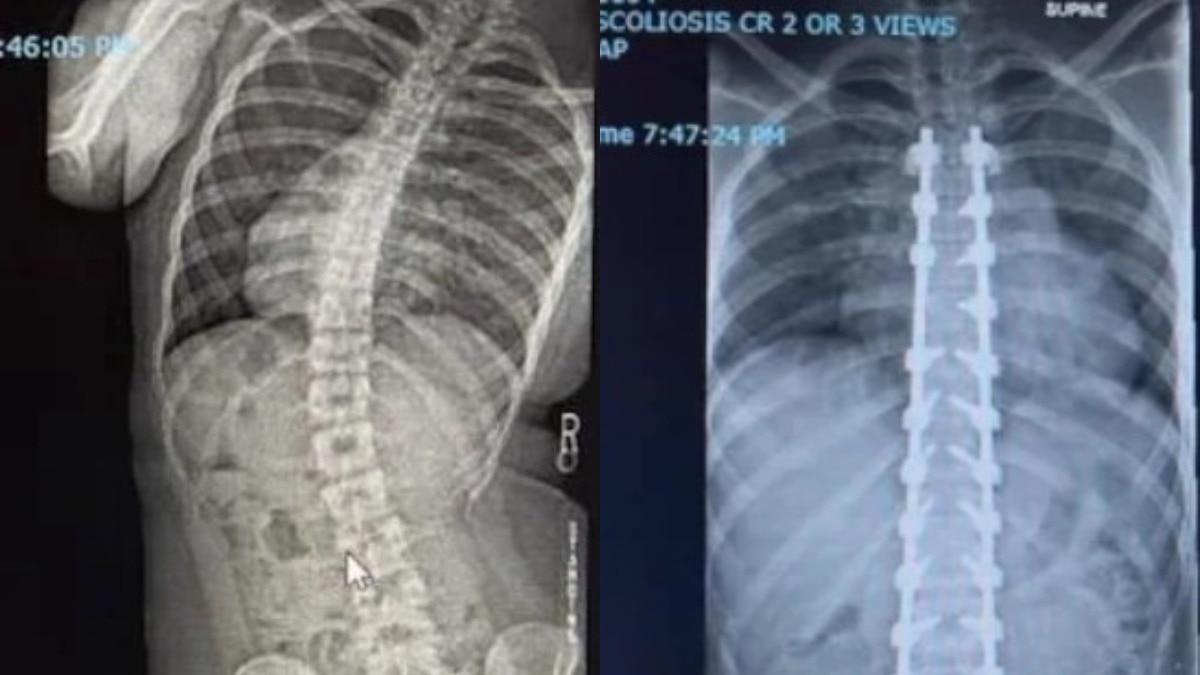

स्कोलियो  इसमें रीढ़ साइड में S या C शेप में मुड़ जाती है (PHOTO:Reddit/r/MadeMeSmile)

सोशल मीडिया प्लेटफॉर्म रेडिट पर एक शख्स ने अपनी रीढ़ की हड्डी की सर्जरी से पहले और बाद की ड्रामेटिक एक्स-रे तस्वीरें शेयर कीं, जो देखते ही देखते वायरल हो गईं. 20 साल के ओलिवर मंडेला ने पोस्ट का टाइटल लिखा-11 मार्च को हुई 6 घंटे की सर्जरी के बाद मैं स्कोलियोसिस से ठीक हो गया.उनकी ये ट्रांसफॉर्मेशन स्टोरी अब तक 21 हजार से ज्यादा अपवोट्स पा चुकी है.

ओलिवर को गंभीर स्कोलियोसिस (S या C आकार की टेढ़ी रीढ़ की हड्डी) की समस्या थी. स्कोलियोसिस यानी जिसमें हड्डी S या C आकार की हो जाती है. डॉक्टरों ने उनकी स्पाइनल फ्यूजन सर्जरी की, जिसमें दो या उससे अधिक वर्टिब्रा को स्थायी रूप से जोड़ दिया जाता है. ओलिवर का कहना है कि सर्जरी के बाद मेरी ज़िंदगी पूरी तरह बदल गई है. पहले सांस लेने में दिक्कत होती थी, लगातार दर्द रहता था और पैरों में लंगड़ाहट आ गई थी. अब मैं बिना तकलीफ़ के सांस ले पा रहा हूं, दर्द नहीं है और एनर्जी भी ज्यादा है.